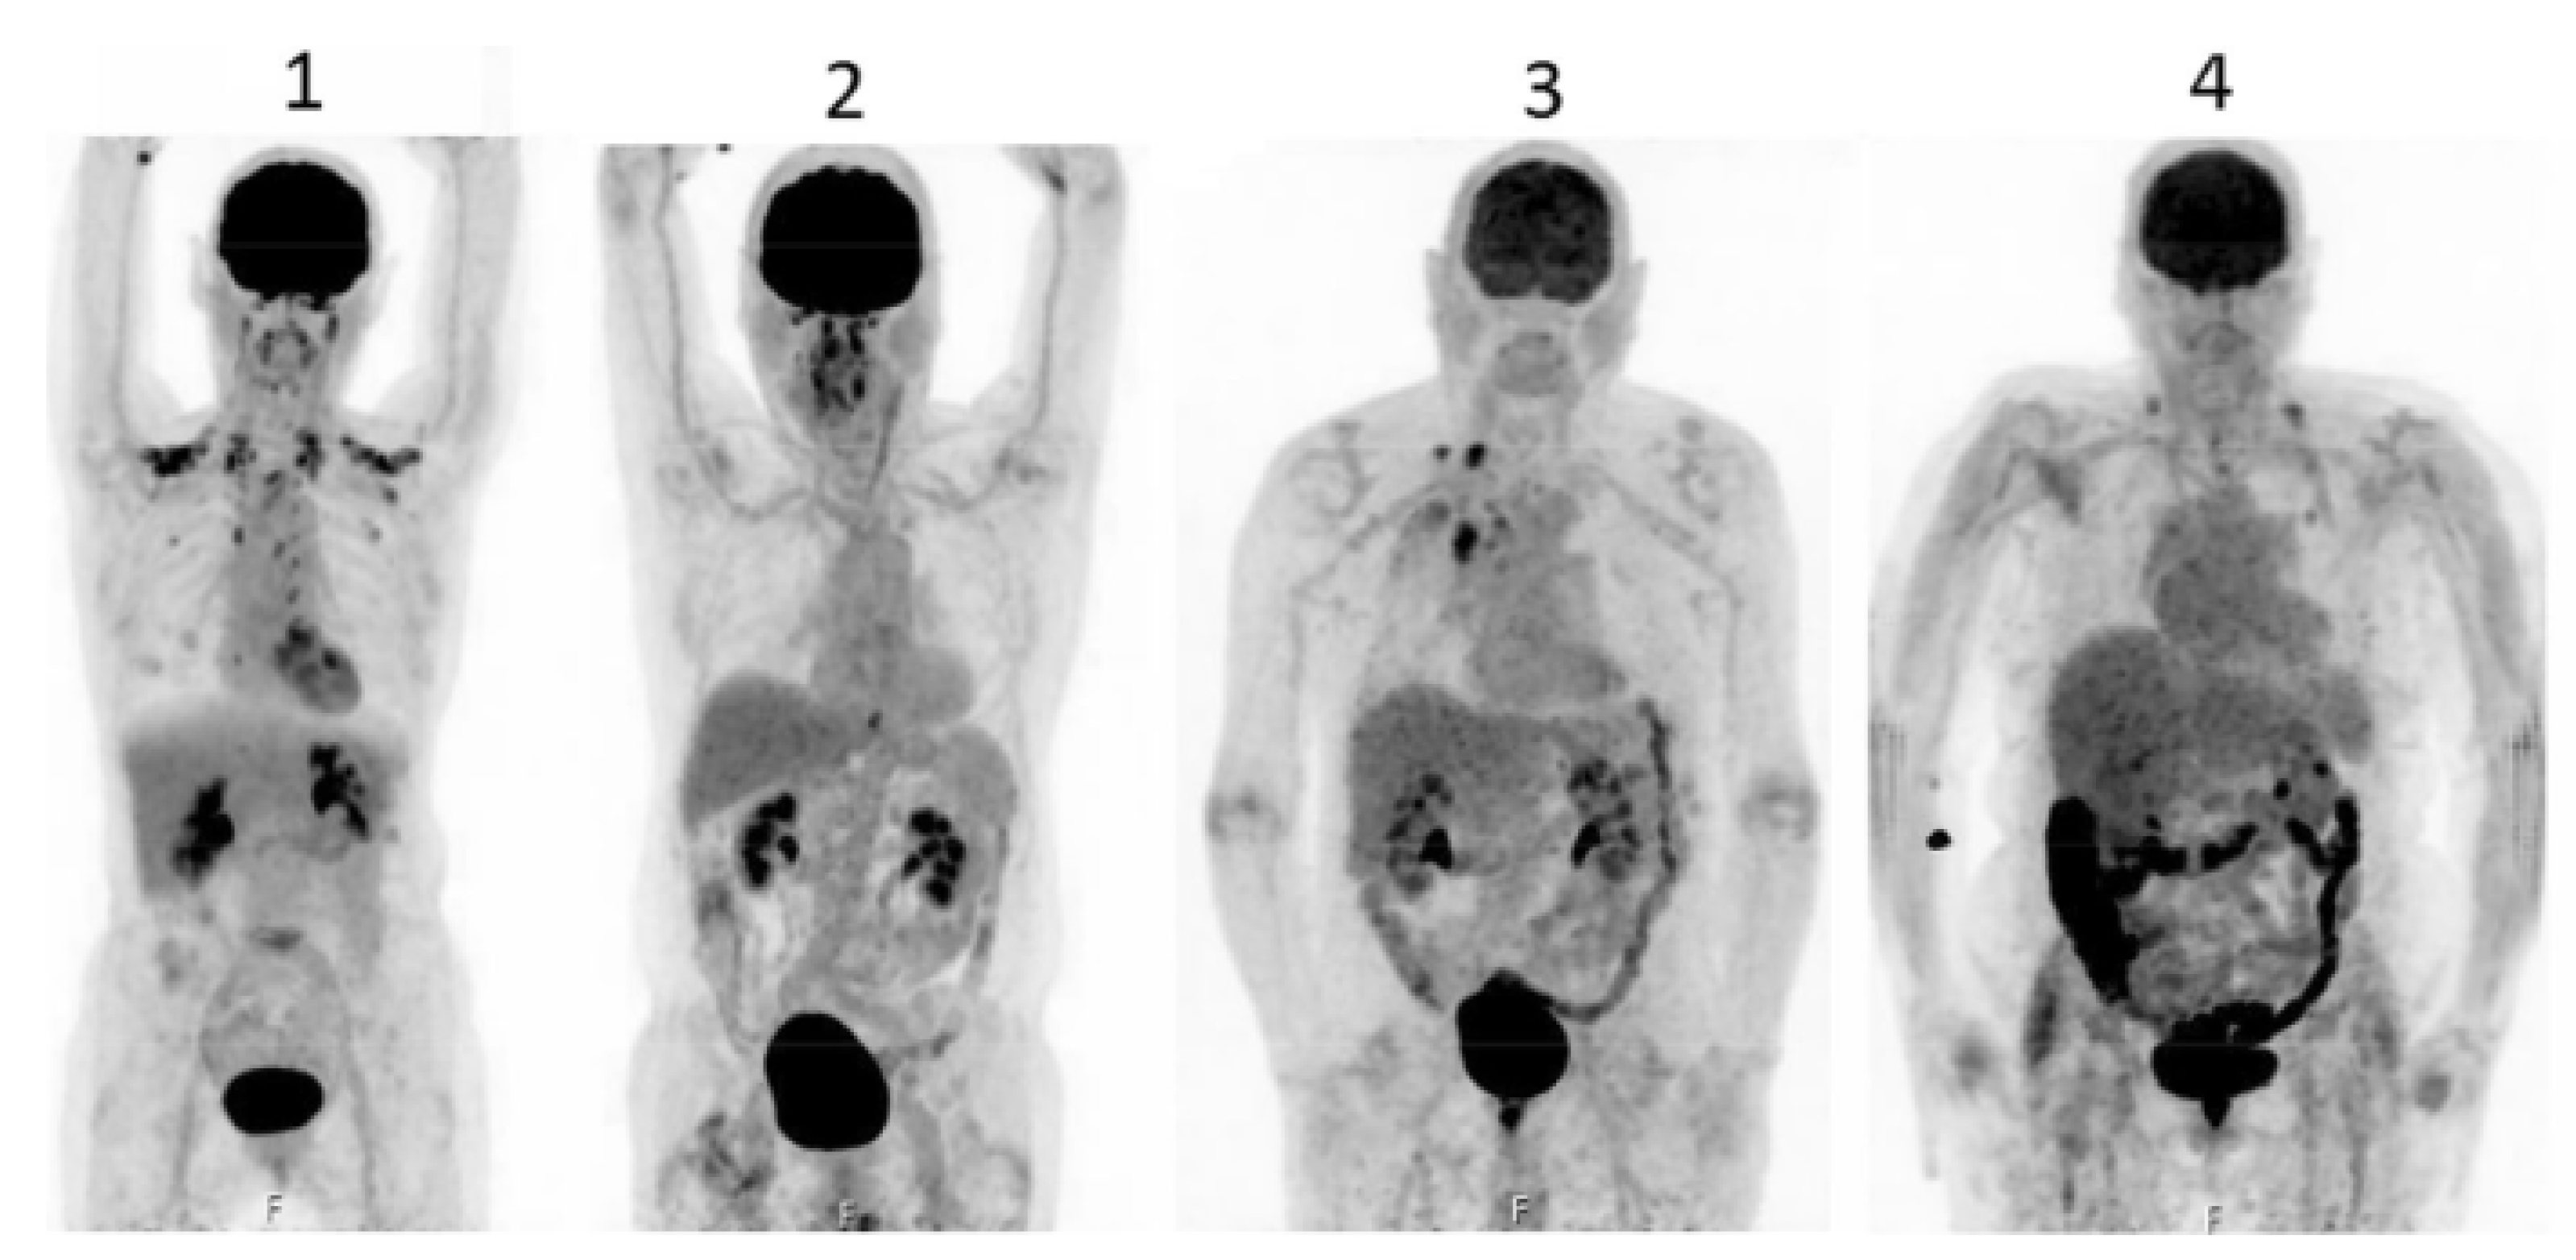

Accumulation of F18-FDG in the large intestine (Figure 4) has been found also in persons who regularly use laxatives [175,176]. SUVmax can even reach levels that simulate those of colorectal neoplasms (Figure 5) in patients with chronic constipation [177].

Figure 4.

PET pictures of early scans (upper row) and of late FDG scans (lower row) after oral administration of laxatives. The arrows in the upper row of PET scans show the different patterns of accumulation of the tracers in the large intestine. From Chen Y-K et al. ([176], with permission).

Figure 5.

Accumulation of radioactivity after intravenous administration in the coecum and ascending colon (upper panel, long arrow) of a patient using anthraquinone laxatives, as demonstrated by the presence of melanosis coli at colonoscopy performed to exclude colon cancer (lower panel, short arrow). From Katsumata R [177].